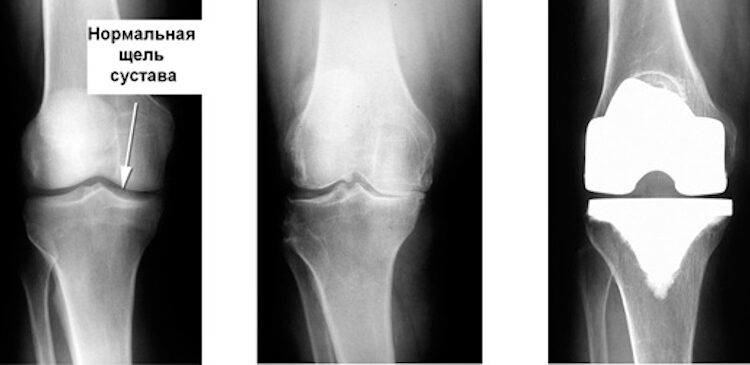

Частичное эндопротезирование предполагает замену только поврежденной части коленного сустава. Чаще всего это его внутренний или наружный отдел. Здоровые структуры – связки, хрящ и непораженные отделы – при этом сохраняются.

При тотальном эндопротезировании выполняется полная замена суставных поверхностей бедренной и большеберцовой костей. При необходимости также устанавливается эндопротез надколенника. Этот метод применяется при распространенном поражении сустава.

Ключевое отличие заключается в объеме вмешательства. При частичном эндопротезировании сохраняется большая часть собственного сустава. А в тотальном сустав заменяется полностью. Это влияет на сроки реабилитации и показания к операции.